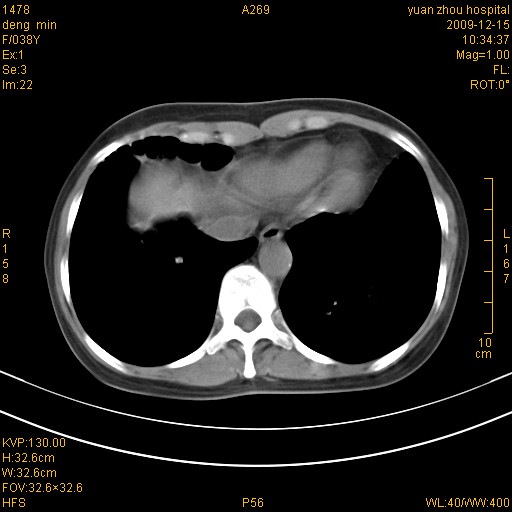

标题: CT23919:F38Y 咳嗽月余 [打印本页]

标题: CT23919:F38Y 咳嗽月余

支扩并感染

右肺中下叶、左肺上叶舌段及左肺下叶支气管扩张合并感染。